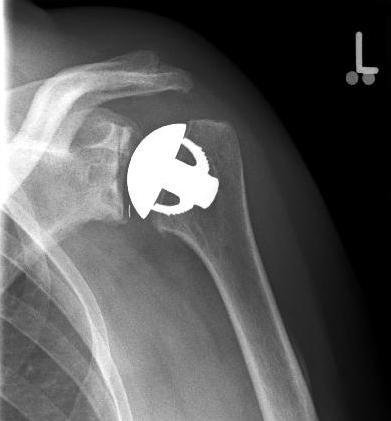

Abbildung3Abbildung4Surface replacement ("cap prosthesis" of the humeral head) in cases of mild omarthrosis and still well-preserved glenoid cavity

links: X-ray image of a cap prosthesis ("surface replacement")

right: cap prosthesis ("surface replacement", type "Durom" Fa. Zimmer)gkl